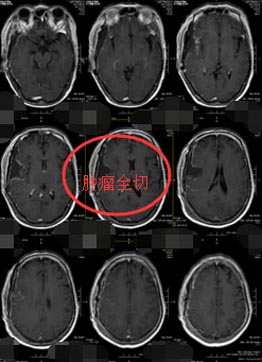

排除手术禁忌症、积极完善术前准备后,由鲁明副院长主刀行“右侧颞部巨大占位性病变切除术”,术中可见肿瘤呈灰褐色,质软,边界不清,血供丰富,肿瘤内侧包绕颈内动脉、后交通动脉,后方与脑干粘连紧密,分离困难,仔细分离鞍区及脑干周围肿瘤,显微镜下全切肿瘤,手术完成顺利。

术后第二天,曾阿姨神志清醒,生命体征平稳,言语对答切题,可遵嘱活动,右上肢手抖较前好转,无腿麻腰痛等不适,病理检查结果示:右侧颞部过渡型脑膜瘤,WHO I 级,CT复查:肿瘤全切。曾阿姨儿子对手术结果非常满意。